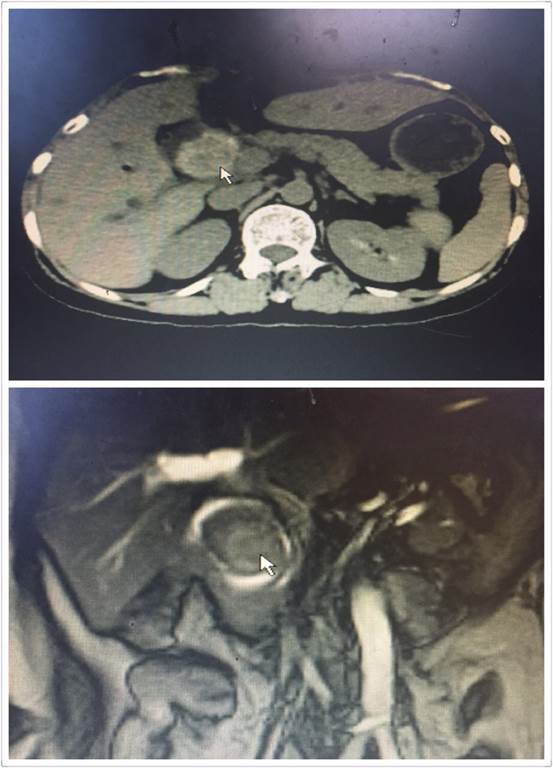

腹腔鏡手術(shù)雖好,但是對于有腹部多次手術(shù)史、腹腔廣泛粘連的患者來說,由于腹腔解剖結(jié)構(gòu)改變,腹腔鏡手術(shù)倒變成了雷區(qū)。近日,肝膽外科收住了一位老年患者,進(jìn)院時(shí)已出現(xiàn)了腹痛、發(fā)熱、黃疸。進(jìn)一步檢查后顯示,患者膽總管結(jié)石阻塞膽管,膽道擴(kuò)張,肝功能差,急需手術(shù)治療(見圖1)。然而這位患者似乎有些“命途多舛”,在這之前她就曾因膽管結(jié)石、腸梗阻在外院作了三次大手術(shù),所以腹部留下了整整長約30CM的手術(shù)疤痕(見圖2)。外院的醫(yī)生了解到該情況后建議直接“開刀”,患者通過打聽得知我院腹腔鏡技術(shù)精湛,遂慕名而來。

圖1